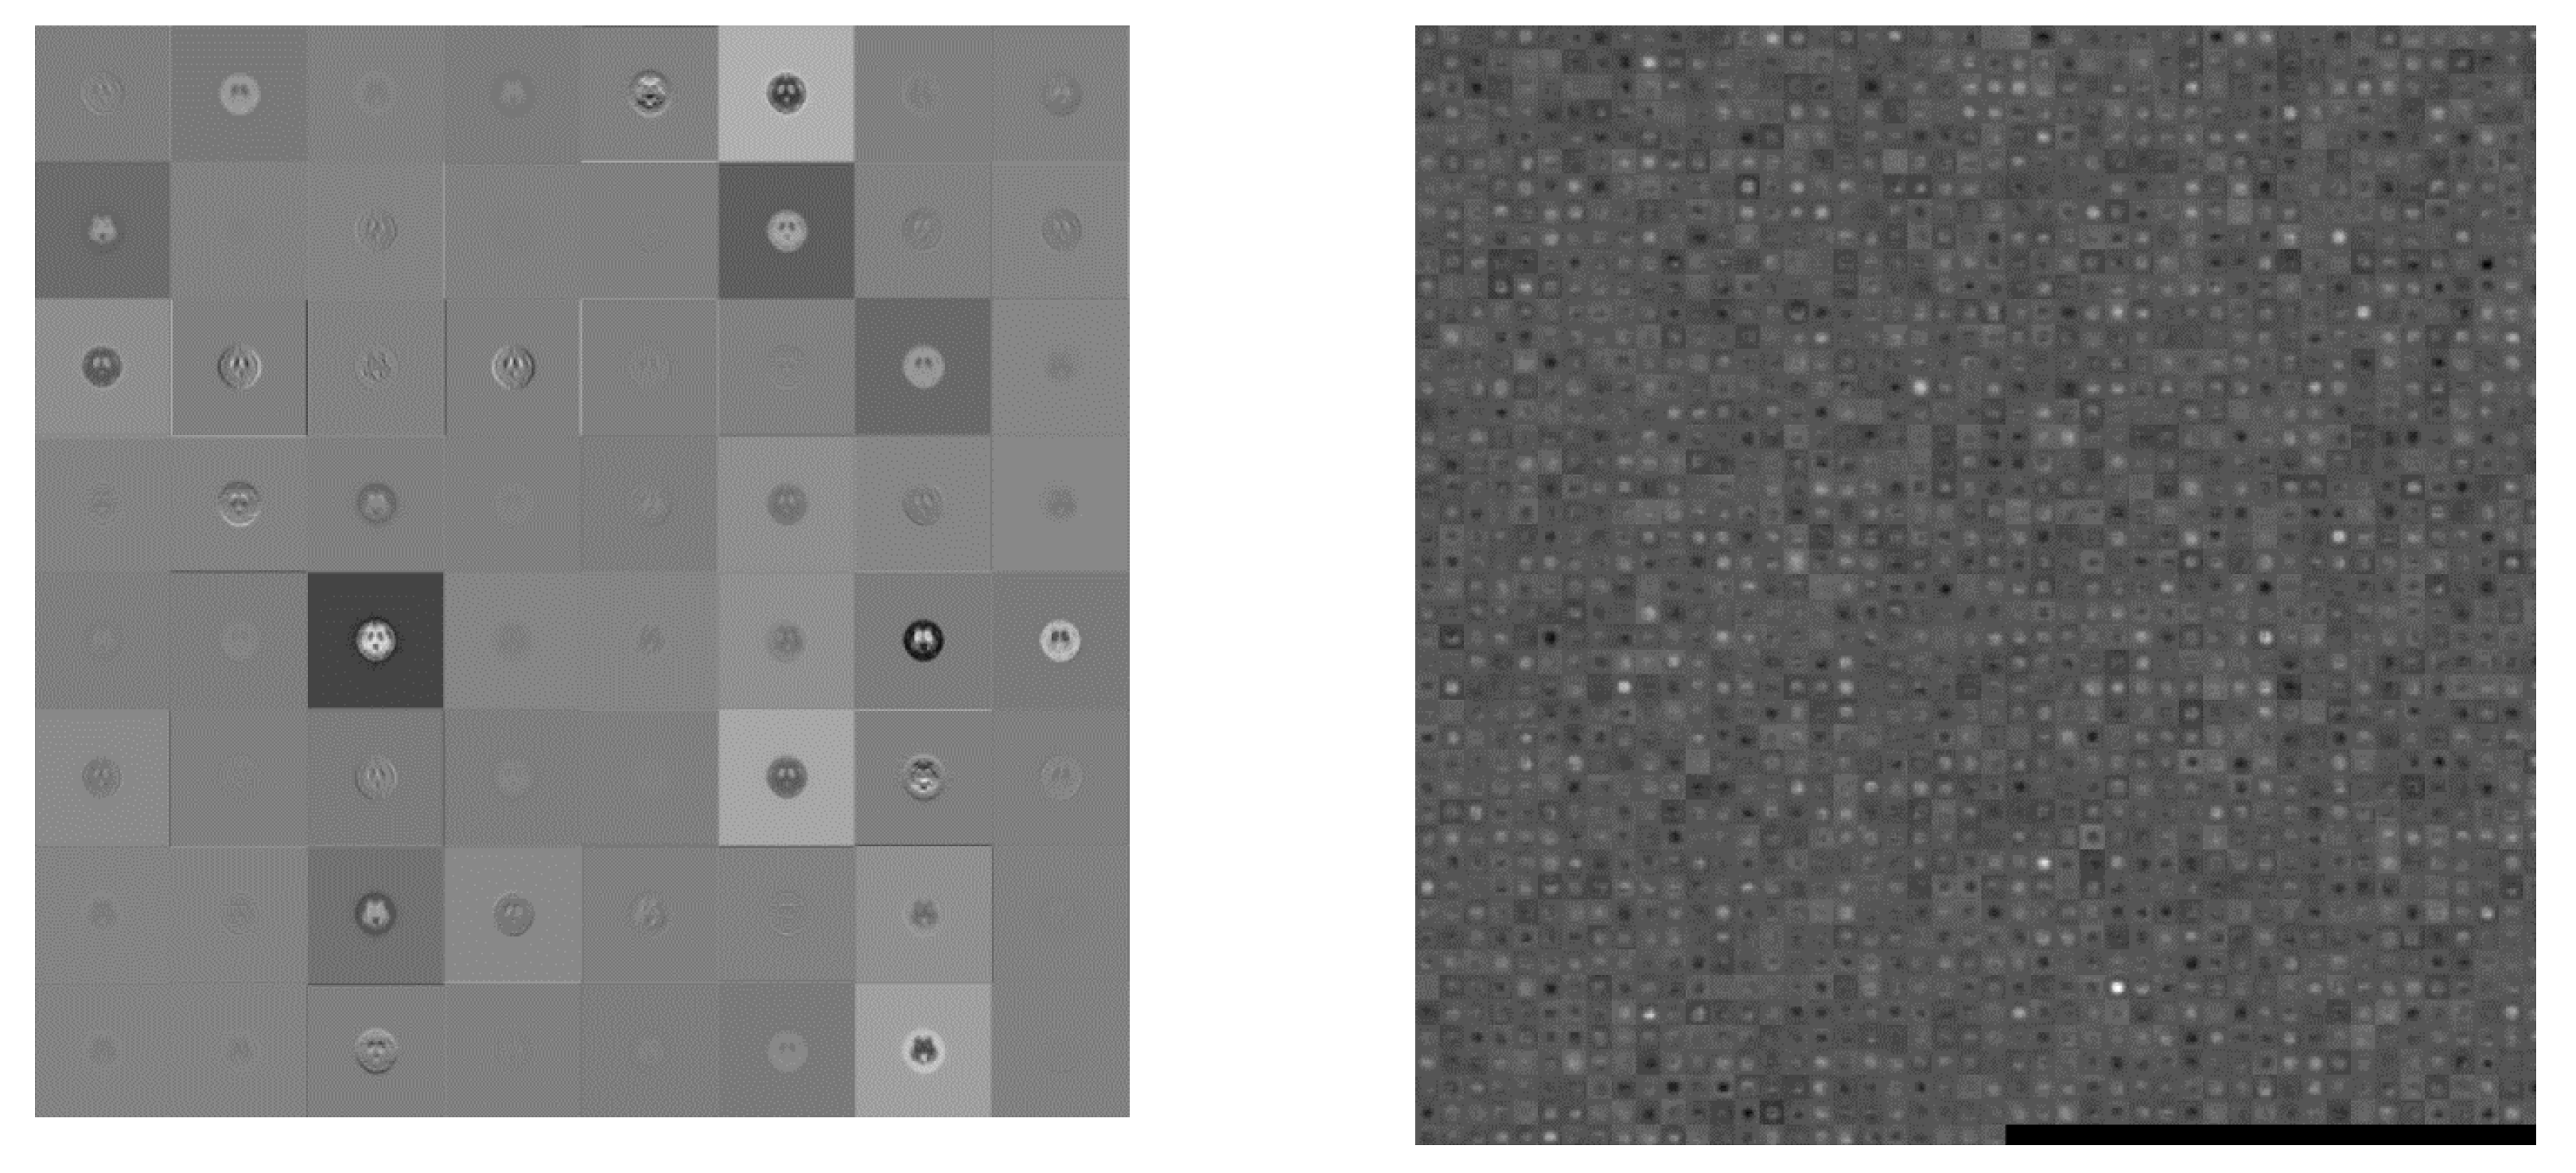

2.4.1. AlexNet

| AlexNet | 227 × 227 | 25 | 227 MB | 25.4 |